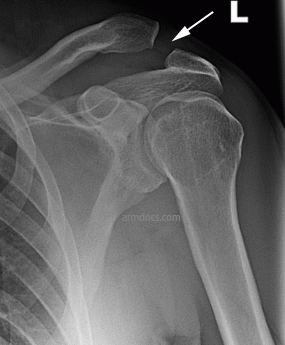

The diagnosis is made from the history of the injury and examination of the shoulder. In case of a sprain the joint may be swollen and tender but in case of a complete separation the shoulder sags down making the outer end of the collar bone stick up and appear more prominent than the other side. X-rays of the shoulder will demonstrate the injury. In some instances comparative x-rays of the both shoulders or load-carrying x-rays may be requested to assess the severity of the injury. Special imaging with an MRI scan is not necessary for diagnosis but may be requested to assess associated injuries to the shoulder.